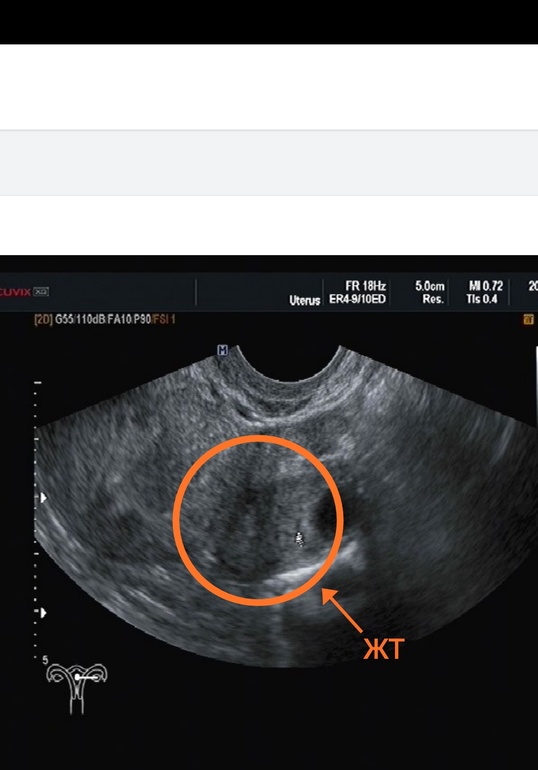

Овуляция была на 12 дц, я в этом уверенна, т.к сильно болел живот где то час-два, а затем просто перестал, и было много ЯБ, так что мой любимый шутил, что я сильно рада его видеть 😂 (хотя не без этого)